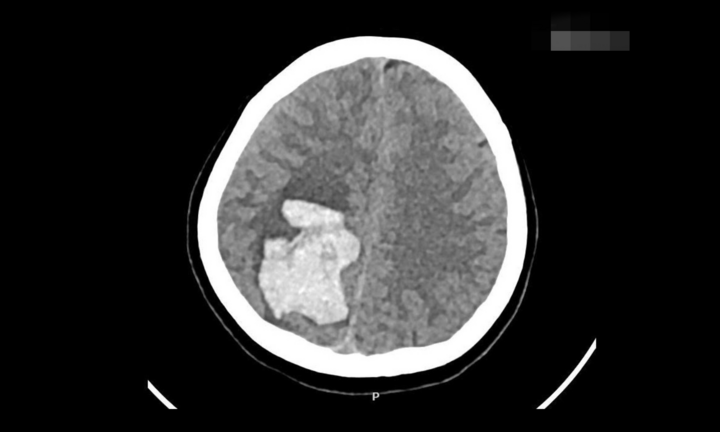

Dưới đây là những hiểu lầm phổ biến về đột quỵ, có thể khiến người bệnh đánh mất cơ hội sống sót:

Nghiên cứu đăng trên chuyên san Stroke Journal cho thấy tỷ lệ đột quỵ ở người từ 18-45 tuổi đã tăng đều đặn trong 2 thập kỷ qua. Đột quỵ không phân biệt tuổi tác. Vì nghĩ mình còn trẻ, khỏe mạnh nên nhiều người trẻ chủ quan khi gặp triệu chứng của đột quỵ như tê, yếu nửa người, nói lắp, đau đầu dữ dội, khiến bỏ lỡ thời gian vàng để điều trị.

Do đó, khi thấy các triệu chứng như mặt bị méo một bên, khó nói hoặc nói lắp, tay chân yếu hoặc không thể nâng lên thì người mắc cần đến bệnh viện ngay. Việc chờ đợi hoặc tự chữa trị ở nhà như cạo gió, uống thuốc cảm, thoa dầu chỉ khiến tổn thương não lan rộng hơn. Mỗi phút trì hoãn điều trị đột quỵ, gần 2 triệu tế bào não sẽ chết đi.